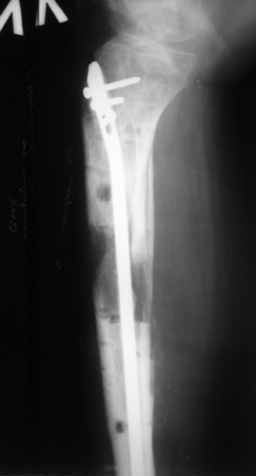

|  |  |  |  status localis на 14.11.08 (В ране визуализируется сухожилие.) | Больной А, 40 лет, находится в клинике с 15.10.08 с диагнозом: Сочетанная травма. Ушиб головного мозга лёгкой степени тяжести. Компрессионные переломы тел 12 грудного и 5 поясничного позвонков без неврологических осложнений. Закрытый внутрисуставной многооскольчатый перелом дистальных метаэпифизов обеих костей правой голени со смещением. Открытый внутрисуставной многооскольчатый перелом дистальных метаэпифизов обеих костей левой голени со смещением (см. Р-граммы). Хронический алкоголизм. Доставлен СМП после падения с 5-го этажа (не суицид). При поступлении состояние тяжелое. Глубокое оглушение. Дыхание самостоятельное, адекватное. Гемодинамика стабильная. По внутренней поверхности левой голени, в нижней трети, рвано-ушибленная рана 10-6 см, из раны выстоит проксимальный отломок большеберцовой кости, рана обильно загрязнена землёй. Интенсивная терапия в условиях реанимационного отделения, вытяжение за правую пяточную кость, параартериальная блокада обеих нижних конечностей, гипсовая лонгета на левую нижнюю конечность, ас-повязка на рану. Через 4 часа после поступления оперирован: после неоднократного промывания раны тёплой проточной водой с мылом, антисептиками, при ревизии определяется земля в канале проксимального отломка на глубину 3 см..., отсутствие надкостницы на концах дистального и проксимального отломков на 3 см. Удалено значительное количество мелких костных фрагментов, перемешанных с землёй, выполнена ПХО раны, резекция проксимального конца большеберцовой кости на 3,5 см, ЧКДО аппаратом Илизарова. Рана не ушивалась. В последующем перевязки раны с "Левомеколь", через 3 недели с момента травмы в ране определялись грануляции, нежизнеспособный конец дистального отломка. 10.11.08 ВХО раны, резекция дистального отломка на 3 см, перемонтаж аппарата наружной фиксации (см. Р-граммы). Отломки сближены на 2 см (остеотомию малоберцовой не делали). В настоящее время (5 сутки после операции) незначительное количество серозного отделяемого из раны, имеется дефект кости 4 см (см. Р-граммы). В последующем склоняемся к перемонтажу аппарата наружной фиксации, остеотомии малоберцовой кости в области повреждения, сближении отломков. По заживлению раны удлинение левой голени на 4 см. Однако, некоторыми высказывалось мнение о необходимости артродеза. Представляем рентгенограммы левой голени при поступлении, после повторного оперативного лечения и фото st.localis на 14.11.08. Будем очень благодарны за критику, комментарии, пожелания и мнения о дальнейшей тактике лечения.

Рентгенограммы прилагаются. Фото местного статуса выложу в ближайшее время.